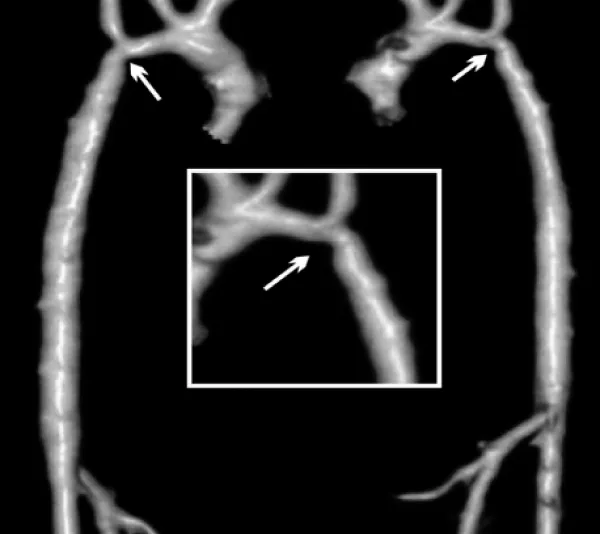

A 5 month-old male, 5 kg weight, with WS phenotype confirmed by FISH test, had an end-to-end anastomosis for severe COA at age one week. He was referred for irritability and poor weight gain. Femoral pulses were absent with upper limb systolic blood pressure of 190 mmHg. A multi-slice CT showed left aortic arch with bi-carotid trunk and recurrent coarctation measuring 1.9 mm in diameter while the transverse arch, the mid aorta, and the aorta at diaphragm level measured 2.8, 3.6, and 5.0 mm respectively (Figure 1). Associated anomalies were moderate right PAS, inguinal hernias, and horseshoe kidney.

Figure 1: Multi-slice CT at the age of 5 months. There is recurrent coarctation of the aorta (arrow) with hypoplasia of the transverse arch extending to the thoracic aorta (see text for diameters at different levels).